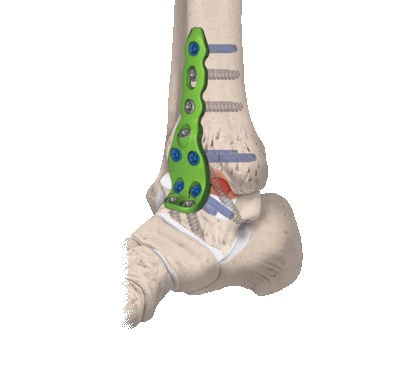

Артродез голеностопного сустава.

Ранее золотым стандартом хирургического лечения был артродез — операция, направленная на полное обездвиживание голеностопа. С одной стороны, она помогала избавиться от хронических болей. С другой — изменяла биомеханику стопы и всей конечности, из-за чего нарушалась динамика ходьбы и нередко возникала хромота. Поэтому от артродеза стали отказываться, а вместо него начали выполнять эндопротезирование.

- Комбинированный. Эта техника подразумевает сочетание в одном хирургическом процессе двух способов: внутрисуставного и внесуставного. Так, хрящевые структуры с сустава полностью счищаются, внедряется аутотрансплантат, который фиксируют специальными металлическими пластинами.

Артродез голеностопного сустава может проводиться как под общей анестезией, так и при спинальной анестезии (обезболивающие препараты вводятся в позвоночник, нижняя часть тела не воспринимает болевых ощущений). В ходе проведения операции врач производит разрез и резецирует сустав. Иногда для сращивания костей врачи используют специальные медицинские винты, шурупы, стальные пластины, стальные стержни или костные трансплантаты. Операция занимает 2 часа, в зависимости от каждого конкретного случая.